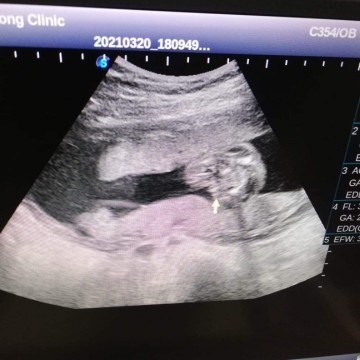

35+3 เด็กหญิง😍

16w หญิงค่ะ

ลูกสาวค่ะ 21w